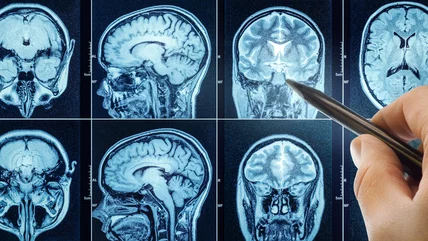

Medical staff need to clearly know what caused the coma from physical examination, laboratory testing, or medical imaging. Guidelines also require a long enough waiting period for drugs or neuromuscular blocking agents to have left the patient's body and for the person to have a normal core temperature and blood pressure.

Next a doctor would need to check for brain stem reflexes like eyes reacting to light or physical touch, eyes turning when the head is turned or ice water is placed into the ear, and reactions to stimulation of the throat. In the absence of these reflexes, physicians would then go on to the third and final check, apnea testing. In apnea testing the patient is removed from a ventilator and checked for signs of breathing for eight to 10 minutes. If there are no signs of breathing, and blood tests show a significant increase in CO2, the patient is diagnosed as brain dead.

In some cases, physicians will carry out other tests for brain death to confirm their diagnosis or when apnea testing is inconclusive. These include imaging of blood flow to the brain using radioactive tracers, ultrasound tests to look for pulsing arteries in the brain, or exams to detect electrical activity. After a diagnosis of brain death a patient would then be declared legally dead and withdrawn from life support or prepared for organ donation depending on patient and family preferences.